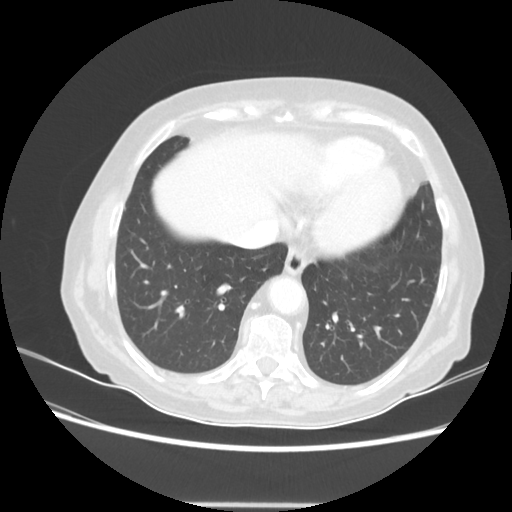

Original VENOUS CT scan

Full window (WL 1023.5, WW 4095 β†’ Low βˆ’1024, High +3071)

Lung window (WL -600, WW 1500 β†’ Low βˆ’1350, High +150)

Mediastinum window (WL 40, WW 400 β†’ Low βˆ’160, High +240)